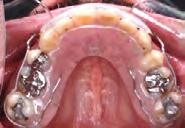

Estudios intraorales, fotografías finales

En la Figura 10 tenemos las líneas medias dentales coincidentes, la corrección de overbite, en la lateral izquierda clase I molar y canina bilateral, una correcta intercuspidación.

Retención

Para la estabilidad se indicó un retenedor circunferencial superior e inferior con cinturón vestibular (Figura 13).

Figura 9. Extraoral de frente y final de inicio y final. Figura 10. Intraorales.

Figura 13. Vista oclusal superior e inferior.